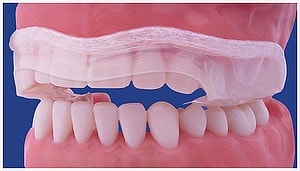

Dezorientációs sín

Általában az alsó fogív fogaira készült átlátszó sínről beszélünk, melynek rágófelszínén átlátszó akrilát van. Súlyosabb állkapocsízületi problémák kezelésénél használjuk. A sín lényege, hogy egyenletes, sima felszínt biztosít a felső fogívvel történő érintkezés során. Ezáltal kiiktatjuk a kóros fogérintkezéseket, relaxáljuk a rágóizmokat, és az ízület a számára legkényelmesebb helyzetbe kerülhet.